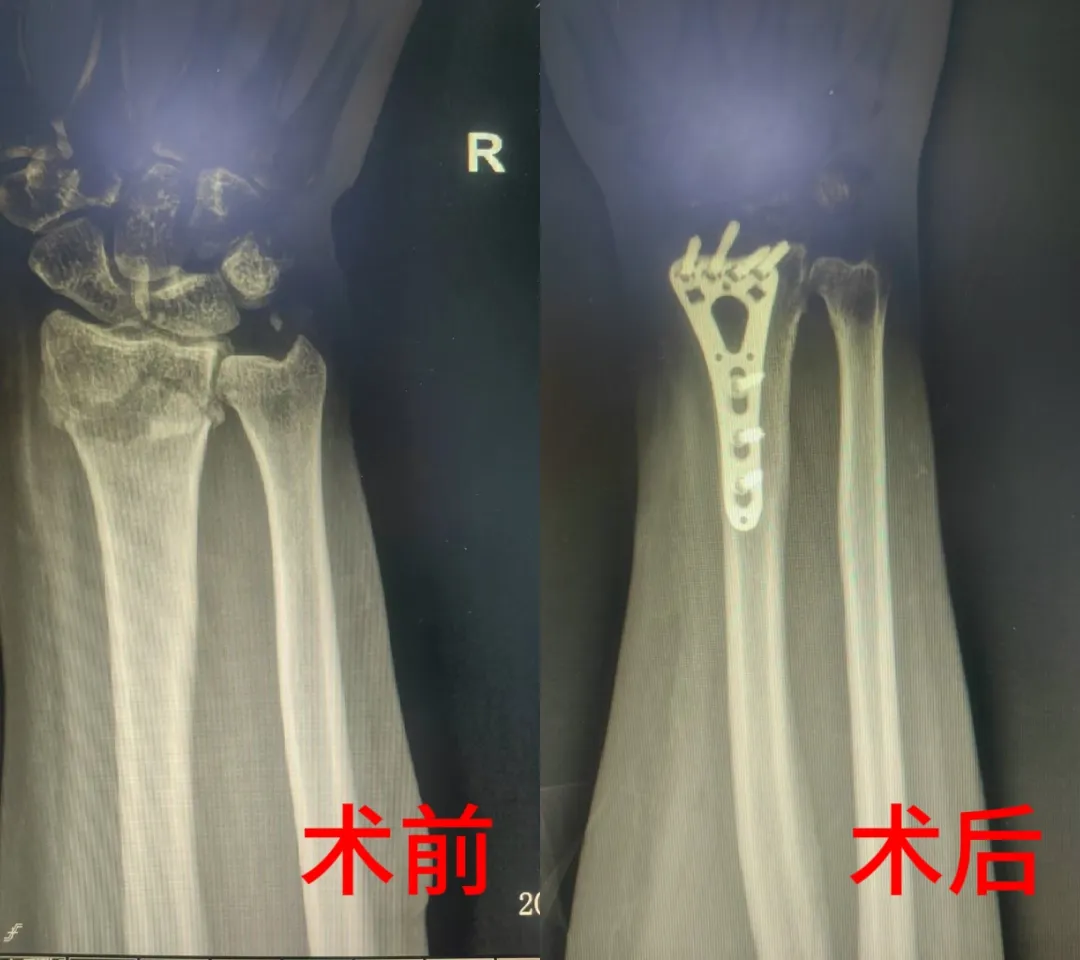

术前进行精准评估,通过X光等影像学检查明确骨折类型及移位程度。早期阶段采取冰敷、药物镇痛等消肿止痛治疗,同时完善术前相关检查,待患肢肿胀明显消退后,根据影像数据制定手术方案,实施切开复位内固定术。术后进行X线复查,确保骨折端达到解剖复位。